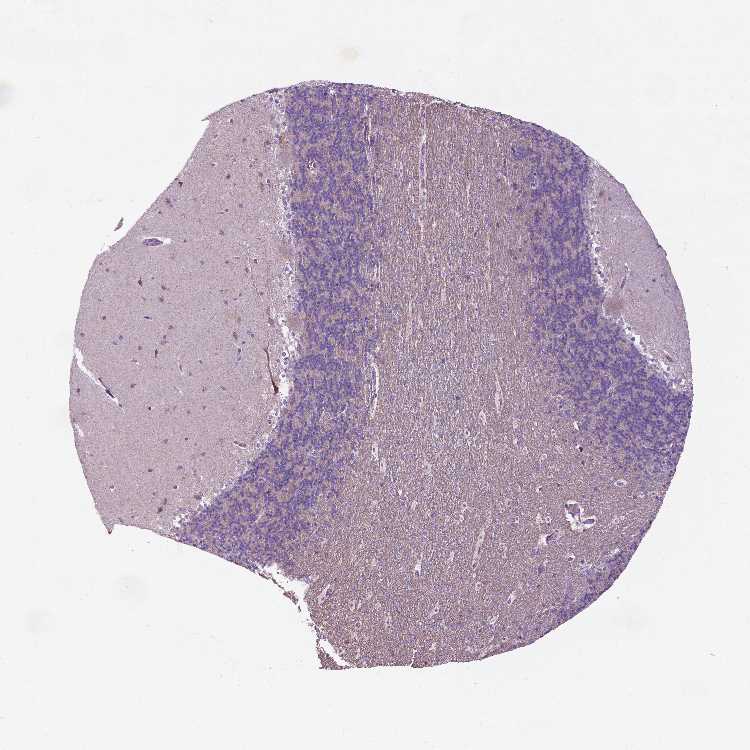

BRAIN CEREBELLUM Show tissue menu

CEREBELLUM - Expression summary

CEREBELLUM - Antibody stainingi

Antibody staining in the annotated cell types in the current human tissue is reported as not detected, low, medium, or high, based on conventional immunohistochemistry profiling in selected tissues. This score is based on the combination of the staining intensity and fraction of stained cells.

Each image is clickable and will lead to virtual microscopy that enables deeper exploration of all samples and also displays staining intensity scores, fraction scores and subcellular localization as well as patient and tissue information for each sample.

Antibody HPA067683

Purkinje cells Not detected

Cells in granular layer Not detected

Cells in molecular layer Low